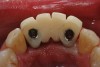

A 53-year-old man presented with localized advanced periodontal disease of the mandibular incisors. Teeth Nos. 23 to 26 exhibited class II mobility because of advanced bone loss (Figure 1). The teeth had migrated out of position over the years, and a diastema had developed between teeth Nos. 24 and 25 (Figure 2). The patient complained about the poor esthetic appearance of these teeth, and he was able to perceive their loss of strength on function as a result of their mobility.

Figure 1  The preoperative clinical condition.

Figure 1